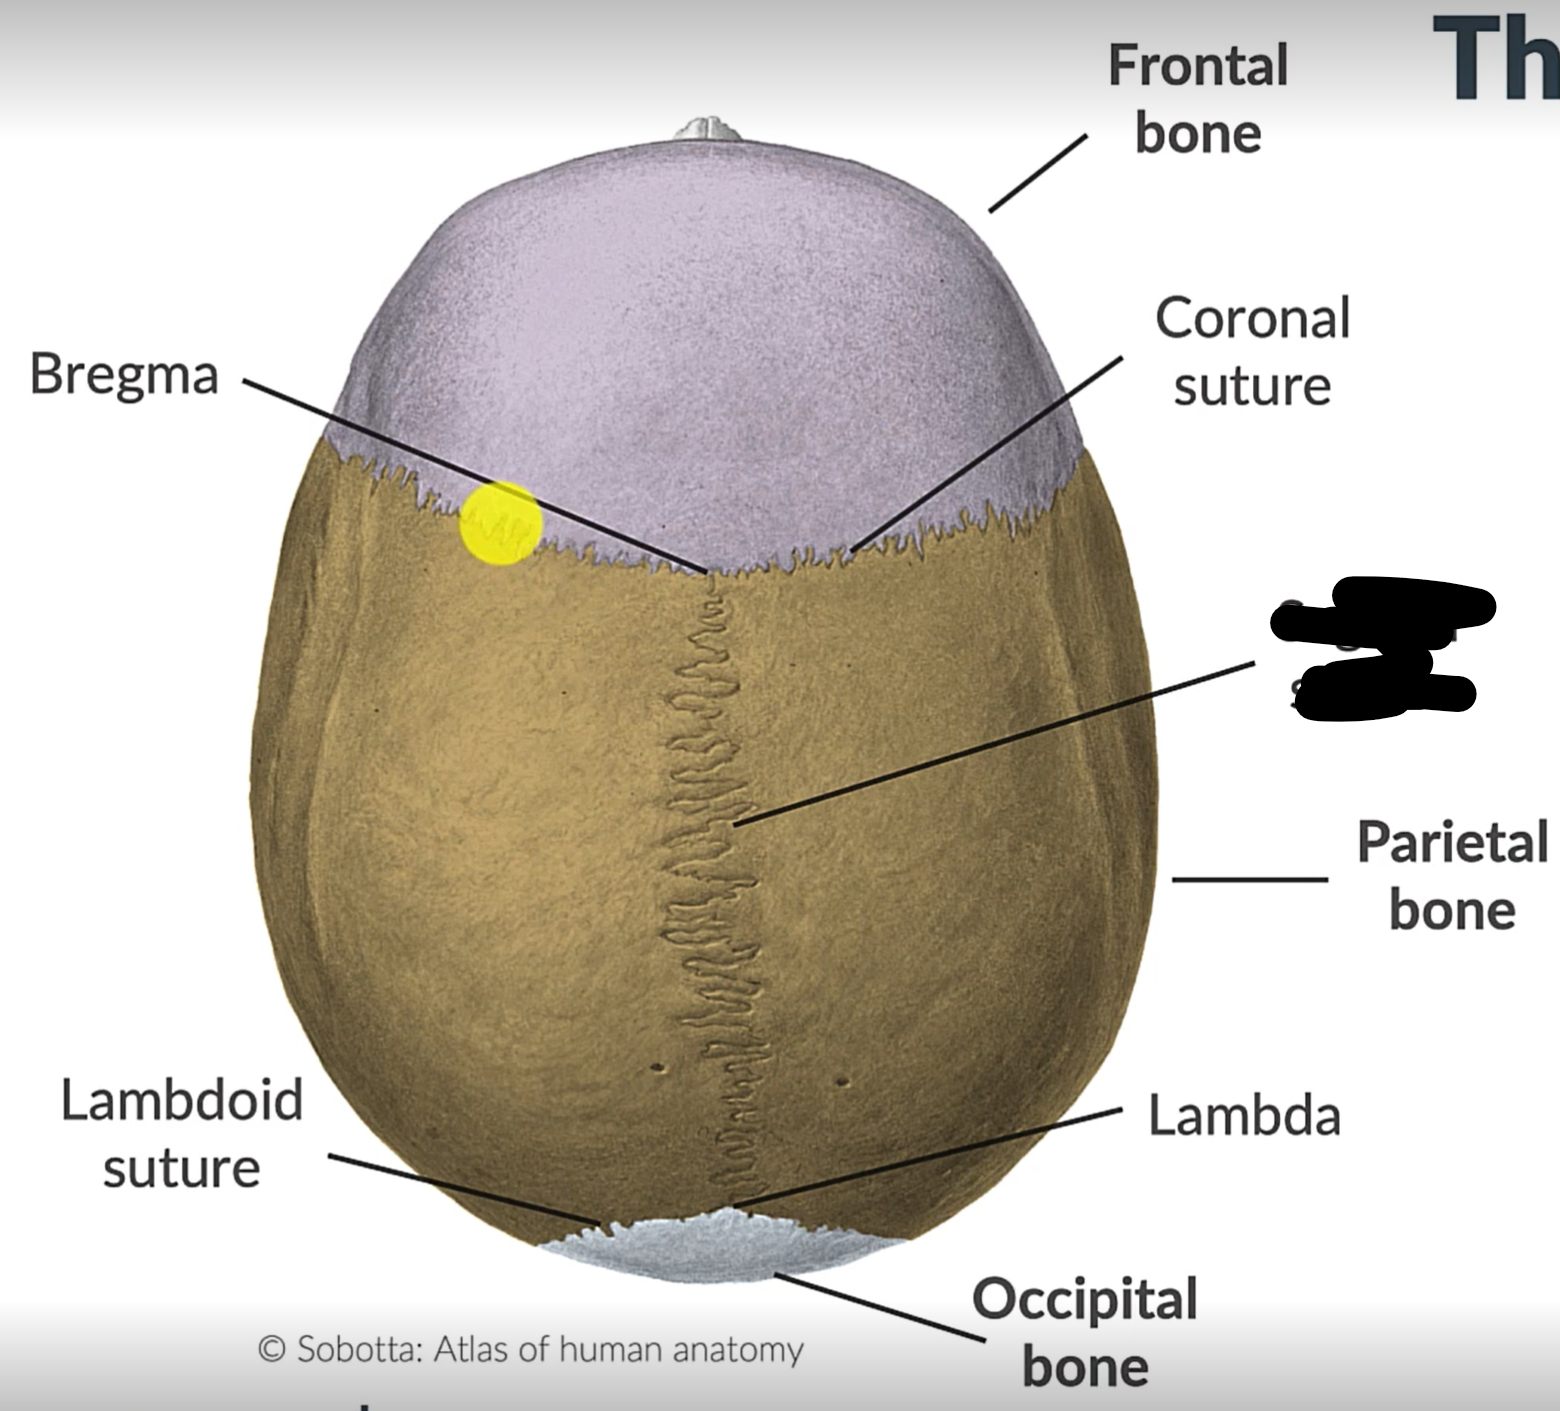

What are the 4 cranial sutures and what do they separate?

Lambdoid - separates occipital from parietal and temporal

Sagittal - extends between parietal bones

Coronal - divides frontal and parietal bones

Squamous - either side of cranium, separates temporal and parietal bones

Sagittal suture

Lambdoid suture

Occipital bone

What is the point where the frontal and parietal bones meet?

Bregma

Lambda